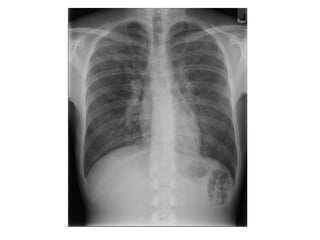

-Features on chest radiographs include ground-glass

opacification, small nodular opacities, “shaggy” cardiac

silhouette, and ill-defined diaphragmatic contours, it has

been reported that 80% of patients with asbestosis have

coexistent pleural disease at chest radiography, fibrous

bands are sometimes seen to radiate inward from the

pleura

(a) PA radiograph of a patient with asbestosis shows “shaggy”

mediastinal and diaphragmatic contours, (b) Localized view of the

lung bases of the same patient further illustrates the diffuse

interstitial opacification

PA radiograph shows diffuse fine nodular and reticular opacification

with irregularity of mediastinal and diaphragmatic contours, the

costophrenic angles are blunted because of pleural thickening